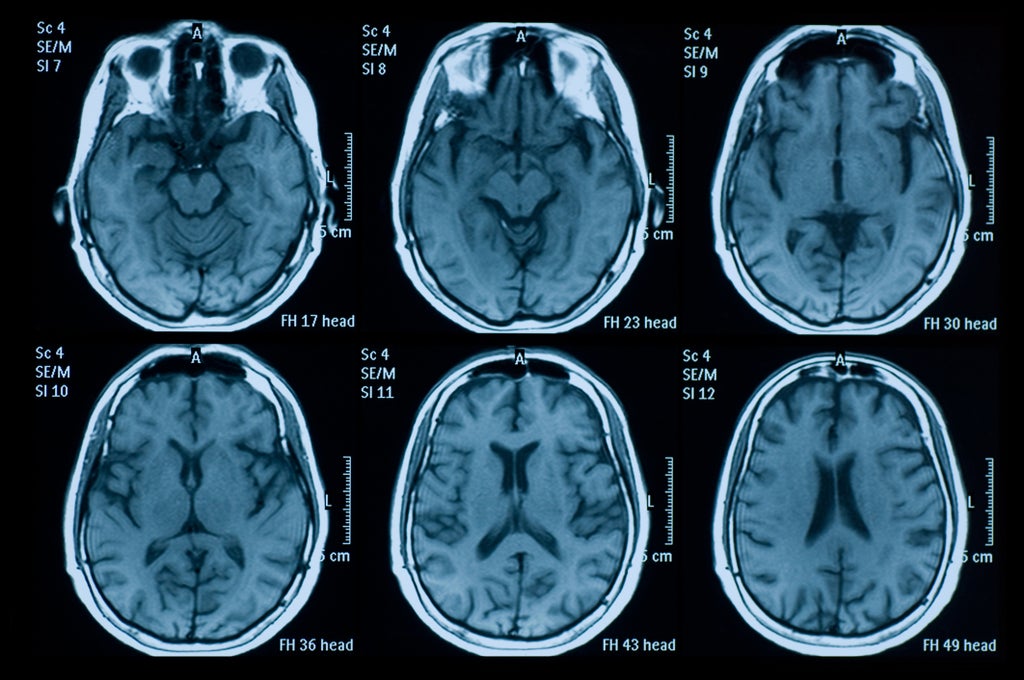

Meanwhile, it is possible to measure brain development with imaging technologies such as ultrasound, magnetic resonance imaging (MRI) and computerised tomography. The development of these technologies has led to a wealth of research on how the brain changes, and each year millions of clinical brain scans are performed worldwide. Despite this progress, there are few measures that are used to aid in monitoring brain development. Why?

In contrast to traditional growth charts, quantifying brain development and ageing comes with a host of technical obstacles. Simply put, there is no tape measure for the brain. This makes it difficult to standardise measures across different studies. The costs and complexity of acquiring brain scans mean the data available to generate reference charts for a single study is limited.

There is still much work to be done before these brain charts can be used as reference tools by healthcare professionals. The underlying dataset contains both ongoing studies, and those that were started as early as 1990 when MRI machines were in a select few places in the world. So the brain charts can constantly be updated, expanded and refined.

As larger datasets become more of the norm, we hope to continue to make our reference charts more inclusive and representative. As brain scanning becomes cheaper and increasingly accessible (even portable), we hope our brain charts will enable more quantitative standards and aid neuroscientific discoveries to parallel these exciting technological advances.